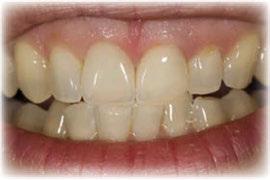

directamente a cabeza de implante para realizar una prótesis dentoalveolar de cerámica de 3 piezas, que equilibraran la oclusión y dieran soporte al labio y la mejilla (Figuras 14-17)

Figura 14. Imagen intraoral frontal postoperatoria al año de la reconstrucción.

Figura 15. Detalle de prótesis dentoalveolar cerámica en visión lateral.

Figura 16. Ortopantomografía postoperatoria.

Figura 17. Resultado final.